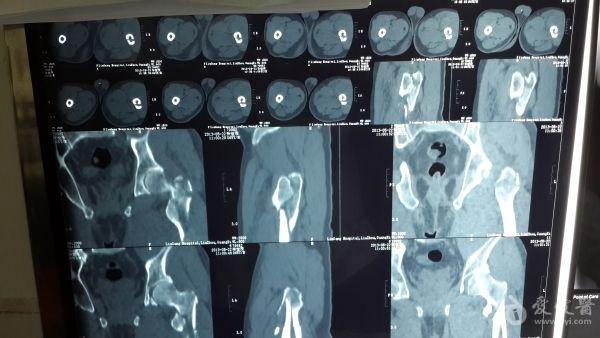

股骨粗隆间粉碎特性骨折的手术方案

男性,65岁